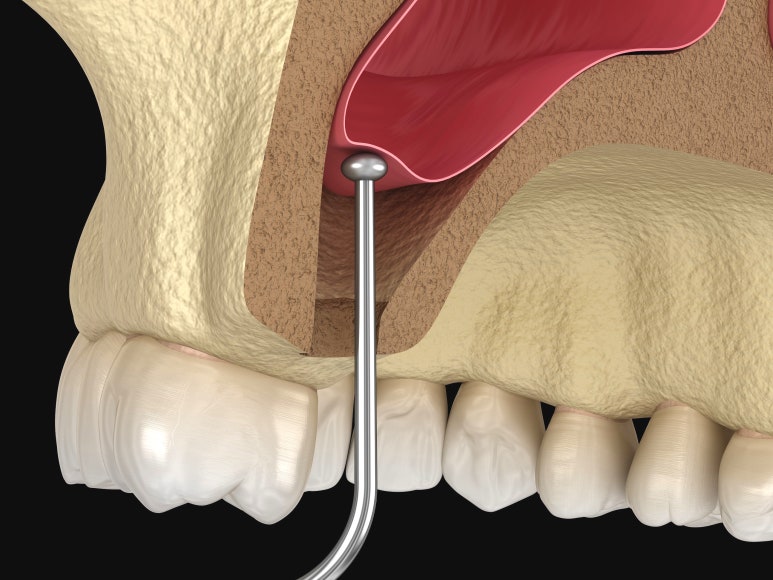

아래서 접근하는 치조정 접근법

크레스탈 어프로치

뼈가 어느 정도 있어서 뼈이식 양이 적고, 이식해야 할 부위에 이상한 구조물이 없다면 '크레스탈 어프로치'로 진행됩니다.

이는 인공치아를 심으려는 위치에 드릴로 구멍을 내어 수직으로 뼈를 이식하는 방법입니다.

절개가 적어 통증이나 멍, 부기 등이 그나마 적은 편이라 할 수 있습니다.

다만 상악동 막을 직접 보면서 시술하는 것이 아니라 의사의 감각에 의존하여 시술해야 합니다. 따라서 무리해서 진행할 경우 막이 찢어질 수 있어 주의해야 합니다.